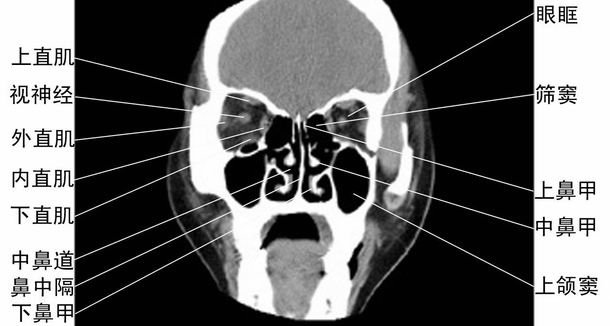

CT冠状位眼眶、鼻腔和上颌窦层面